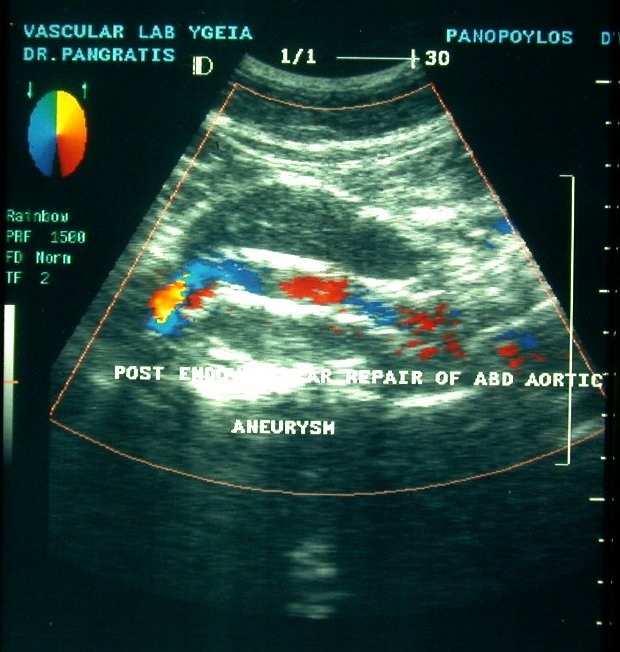

2. Ç åíäáããåéáêÞ áíôéìåôþðéóç êáôÜ ôçí ïðïßá ôïðïèåôåßôáé áðü ôçí ìçñéáßá áñôçñßá åíôüò ôïõ áõëïý ôïõ áíåõñýóìáôïò , åíäáõëéêüò íÜñèçêáò (stent) åðåíäåäõìÝíïò ìå åéäéêü õëéêü ãéá áðïêëåéóìü ôïõ áíåõñýóìáôïò.

Ç ôå÷íéêÞ áõôÞ åéóÞ÷èç êáé Ýãéíå ãéá ðñþôç öïñÜ óôçí ÅëëÜäá óôï íïóïêïìåßï «YÃEIA» áñ÷Ýò ôïõ 1995 áðü ôçí ïìÜäá åíäáããåéáêÞò ÷åéñïõñãéêÞò (Ð.ÌðÜëáò, Í.ÐáãêñÜôçò) êáé åîáêïëïõèåß íá ãßíåôáé ìå Üñéóôá áðïôåëÝóìáôá.

H äéÜñêåéá ôçò åðÝìâáóçò åßíáé 100 +- 30 ëåðôÜ êáé ï ÷ñüíïò ðáñáìïíÞò óôï íïóïêïìåßï åßíáé 3-4 çìÝñåò .

Ç áíôéìåôþðéóç ôïõ áíåõñýóìáôïò êïéëéáêÞò áïñôÞò äé åíäáããåéáêÞò ÷åéñïõñãéêÞò áðïôåëåß ìÝèïäï ãéá åðéëåãìÝíïõò áóèåíåßò , áóèåíåßò õøçëïý êéíäýíïõ êáé ðïõ äåí èá çäýíáíôï íá ÷åéñïõñãçèïýí ìå ôçí êëáóéêÞ ìÝèïäï .

Åí ôïýôïéò ìå ôçí áðïêôçèåßóá äéåèíÞ êáé çìåôÝñá åìðåéñßá ïé åíäåßîåéò åêôÝëåóçò ôçò íÝáò áõôÞò ìåèüäïõ äéåõñýíïíôáé þóôå íá ðåñéëáìâÜíåé áóèåíåßò íåùôÝñáò çëéêßáò êáé óå êáëÞ ãåíéêÞ êáôÜóôáóç.

Ïé ÅíäáããåéáêÝò åðåìâÜóåéò óå áíåýñõóìá ôçò êïéëéáêÞò áïñôÞò (ÁÊÁ) õðåñôåñïýí ôçò êëáóóéêÞò åã÷åéñÞóåùò êáè üóïí ãßíåôáé äé åëá÷ßóôïõ ôñáýìáôïò, ç ðáñáìïíÞ ôïõ áóèåíïýò óôï íïóïêïìåßï åßíáé âñá÷åßá, áðïöåýãïíôáé ïé óåîïõáëéêÝò äéáôáñá÷Ýò óå Üíäñåò êáé ç åðÜíïäïò óôéò êáèçìåñéíÝò åíáó÷ïëßåò åßíáé ôá÷ýôáôç.

Ç éäÝá ôçò áðïêáôÜóôáóçò ôïõ áíåõñýóìáôïò ÷ùñßò áðïêÜëõøç êáé áðïêëåéóìü ôçò áïñôÞò èåùñåßôáé üôé ìðïñåß áêüìç íá ìåéþóåé ôçí íïóçñüôçôá êáé ôçí èíçôüôçôá. Åôóé õðÜñ÷åé óõíå÷Þò åîÝëéîç ìå ôçí ÷ñçóéìïðïéïýìåíç ôå÷íéêÞ áíÜðôõîç êáé äïêéìáóßá íÝùí óõóôçìÜôùí , åê ôùí ïðïßùí ôá ðåñéóóüôåñá åìöáíßæïíôáé áðïôåëåóìáôéêÜ óôïí áðïêëåéóìü ôïõ áíåõñýóìáôïò áðü ôçí êõêëïöïñßá .